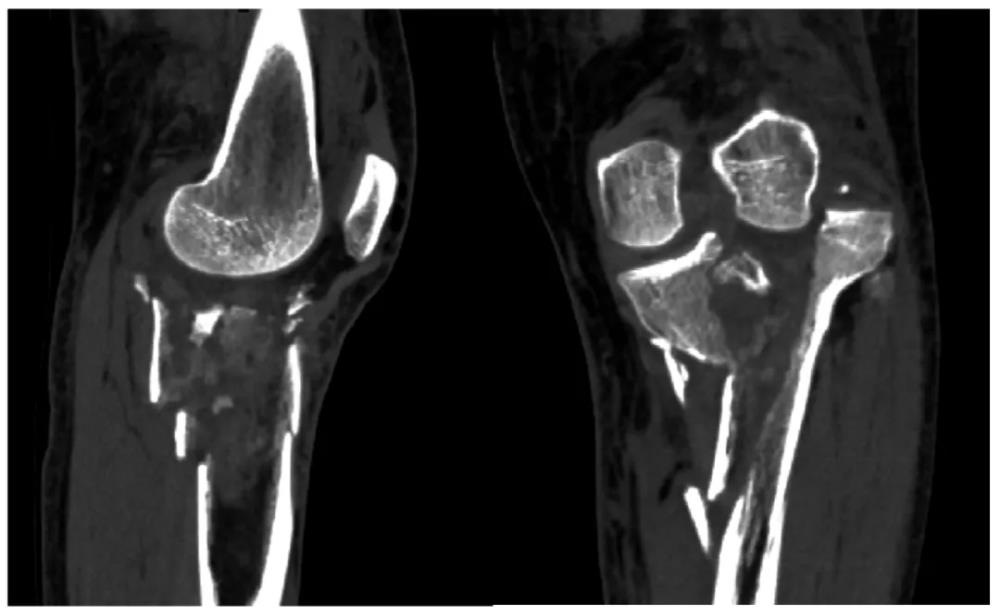

当严重的粉碎性关节骨折遇上数字化医疗,会发生怎样的化学反应?近日,玉林市中西医结合骨科医院膝关节病与运动损伤科联合医学3D打印临床中心,成功实施了一例高难度左胫骨平台粉碎性骨折修复手术。通过1:1的骨骼复刻模型,医生团队在术前就对骨折分离移位“了如指掌”,为患者带来了真正的个性化、精准化治疗。

56岁的樊女士怎么也没想到,一次意外竟让她的左膝遭遇了如此严重的创伤。入院时影像检查结果触目惊心:左胫骨上段及胫骨平台粉碎性骨折,伴有股胫关节失稳。胫骨平台是膝关节重要的负重结构,粉碎性骨折后关节面平整度直接决定术后膝关节功能恢复情况,若复位不佳、固定不稳,极易引发创伤性关节炎、关节僵硬、行走疼痛、跛行等终身后遗症,严重影响中老年患者生活质量。

精准诊断:肉眼可见,左胫骨上段及胫骨平台呈粉碎性骨性结构中断,骨块分离情况严重;

关节评估:关节面粉碎骨折,关节面塌陷,外侧关节面向外上脱位,内侧关节面出现明显倾斜。

以前只能在电脑屏幕上通过二维或三维重建图像去想象,现在有了这个1:1的实体模型,就像是拿着‘破碎的瓷器’在拼图。通过实体模型,团队可以进行模拟手术,预演螺钉的进钉点、角度和长度,极大地提高了手术的精准度和安全性。